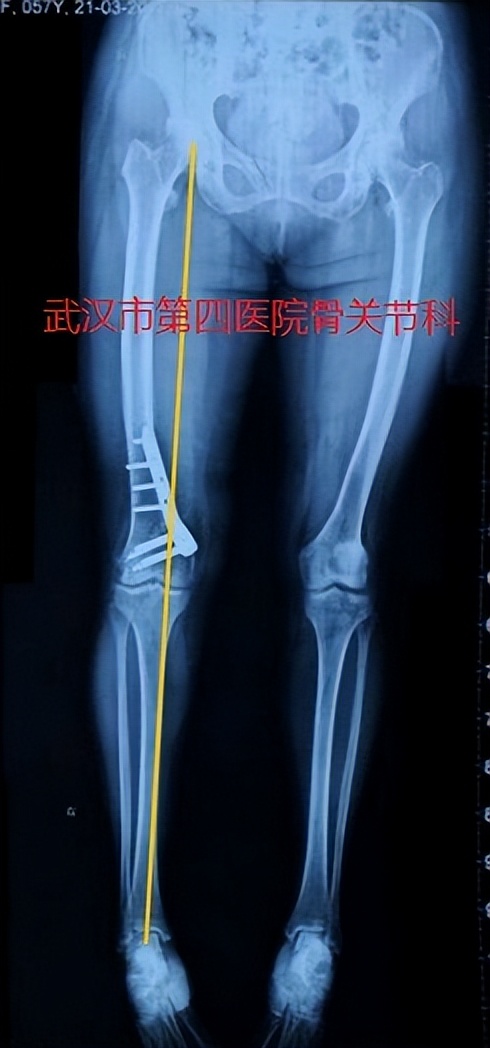

2.保膝手术-截骨手术:如果膝关节骨关节炎合并有关节外畸形,可以考虑行截骨矫正畸形,细分为股骨侧、胫骨侧的畸形矫正。

保膝手术:股骨远端截骨术

保膝手术:胫骨近端截骨术